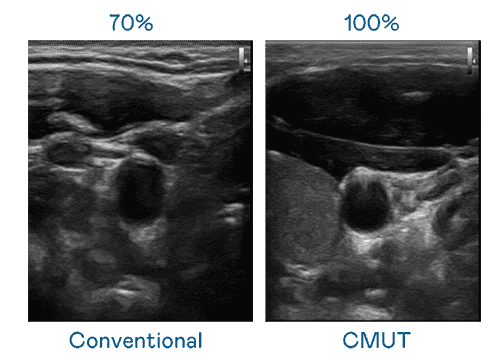

CMUT 技术是一种用电容式微机电元件来产生超音波讯号的技术。。。与传统 PZT 压电式技术相比,,,CMUT 频宽增加 30%,,,更宽频的超音波讯号让影像解析度大幅提升,,,是实现高影像品质医疗超音波扫描、、促进精准医疗发展的关键技术。。。。

大频宽带来超清晰影像

超音波影像的解析度高低,,首先取决于探头能发出的讯号频宽。。。。彩霸王 CMUT 可提供高清晰的超音波讯号,,,提供高频宽、、、高灵敏度、、、、影像纹理细节更高的超音波影像,,,,协助医护人员缩短影像判读时间及利用精准的医疗影像进行诊断。。。。